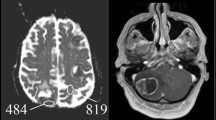

BM of SCLC and NSCLC as examples for Ki67 high and Ki67 low BM

As BM of NSCLC and SCLC mainly differed in their proliferative capacity and the distinction of these two lung cancer types is of major clinical relevance, we further analysed their MRI and histological parameters. BMs of SCLC (n = 8) were represented by the Ki67high BM features, while NSCLC BM (n = 30) showed the pattern of the Ki67low group (p = 0.0119, Fig. 5a). BMs of SCLC were larger (p = 0.0008, Fig. 5a) and showed a smaller peritumoural oedema width (p = 0.0148, Fig. 5a) than BM of NSCLC. Additionally, BM of SCLC showed stronger signs of diffusion restrictions by higher DWICNR signals (p = 0.0329, Fig. 5a) and lower nADCmean values (p = 0.0017, Fig. 5a). On histological level, cell density (assessed by DAPI staining) was increased in BM of SCLC compared to BM of NSCLC (p = 0.0057, Fig. 5a).

Imaging and histopathologic features differ in NSCLC versus SCLC brain metastasis. a Comparison of magnetic resonance imaging features and histopathological parameters in non-small-cell lung cancer (NSCLC) and small-cell lung cancer (SCLC) brain metastases. According to our findings, SCLC (d) usually show stronger signs of diffusion restrictions with reduced values in the ADC map, a bigger tumour size as well as a small peritumoural oedema rim compared to brain metastasis of NSCLC (b). Nevertheless, there are brain metastases that do not reflect these typical morphological findings, exemplified on a NSCLC brain metastasis (c)